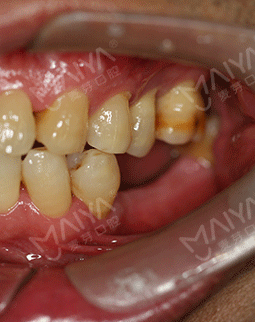

由于职业原因,特别爱好摄影和旅游。去年年底到今年6月,和朋友们分别去了南极和北极,我把这次南北极之旅称之为“南征北战”。尽管今年已经58岁了,热爱冒险又健谈的我和同龄人相比起来却像一个40多岁的人。但由于年轻时对口腔保护意识的薄弱,导致了现在口内5颗牙缺失,大家都想不到吧?别人是缺前牙,我是缺大牙,这大牙可是咀嚼食物的主要牙齿,所以我很多时候吃饭都是囫囵吞枣,对饮食生活造成了相当大的困扰。吃东西费劲,很多时候朋友邀约出去聚会,却只能眼睁睁的看着大家享受美食。随着年龄的增长,缺牙造成的营养吸收不均衡,在饮食和身体健康上带给我的是双重困扰。有人劝我镶牙,但活动牙我看不上,固定牙又不适合伤害健康的牙齿,思前想后,还是决定种牙。

由于职业原因,特别爱好摄影和旅游。去年年底到今年6月,和朋友们分别去了南极和北极,我把这次南北极之旅称之为“南征北战”。尽管今年已经58岁了,热爱冒险又健谈的我和同龄人相比起来却像一个40多岁的人。但由于年轻时对口腔保护意识的薄弱,导致了现在口内5颗牙缺失,对饮食生活造成了相当大的困扰。吃东西费劲,很多时候朋友邀约出去聚会,却只能眼睁睁的看着大家享受美食。随着年龄的增长,缺牙造成的营养吸收不均衡,在饮食和身体健康上带给我的是双重困扰。

我虽然走遍大江南北,也看遍了大江南北的风光。这本是羡煞旁人的事,但对我来说,却有许多遗憾。20年前牙齿就开始脱落了,但当时科学、技术都没有达到现在的标准,自己也没有太在意,如今随着生活品质的提升,科学、技术的提高,对恢复牙齿的需求也变得越来越迫切。